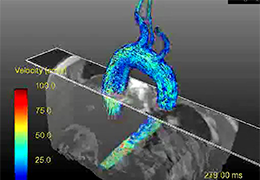

成像智能。

Eclipse 成像智能功能提供强大的处理能力和最佳质量的影像,同时减少质量错误并提高剂量效率。

凭借 AI、专有算法和先进的影像处理能力,提供出色的影像质量和无与伦比的诊断信心。